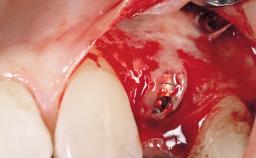

Immediate Flapless Placement of an Implant in a Maxillary Left Central Incisor Site

A 29-year-old female patient presented for treatment to replace the upper left central incisor tooth with an implant- supported restoration. The tooth had been intermittently symptomatic for the previous 12 months. The tooth had originally suffered trauma about 15 years previously. Several endodontic treatments had been performed, including an apicectomy procedure to retain the tooth. The patient was healthy and a non-smoker. She had reasonable expectations in regard to esthetic outcomes and the risk of marginal tissue recession following treatment. At medium smile, the gingival margins of the upper teeth were visible, with a display of 3 to 4 mm of the gingival margins. Gingival recession of tooth 21 and a discrepancy in the gingival levels between teeth 11 and 21 was observable during normal speech and smile.

Placement Protocol Immediate implant placement

Socket Morphology Single-root socket

Socket Integrity Damage to one or more bone walls

Bone Volume Damage to one or more socket walls